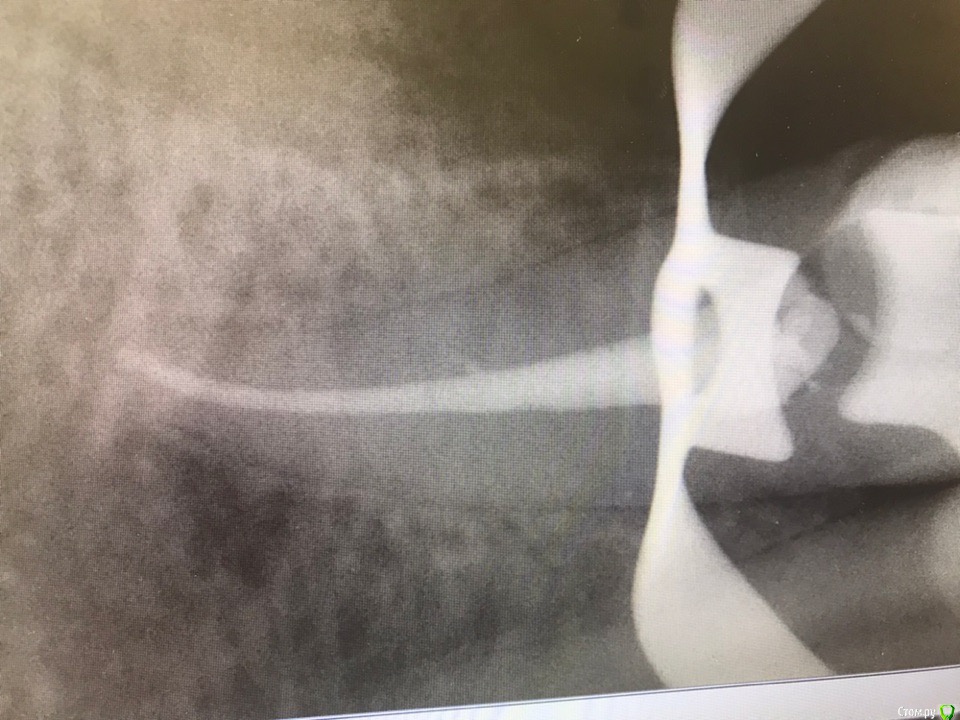

1586Doc Опубликовано 3 мая, 2019 Поделиться Опубликовано 3 мая, 2019 Еще раз спасибо за ответ.Подскажите .Сразу купить не могу и инжектор и плагер. Стоит выбор что первое.Пломбировка чисто инжектором думаю у меня не приживется. Может купить термоплагер и чисто вертикалить? на сколько это ускорит работу в сравнении с латералкой?тут скорее вопрос насколько вы качественно делаете латеральную. Если делать ее как положено времени уходит много. Я использую комбинированный метод. Когда приноровился, выходит достаточно быстро. Расход очень не большой, качество пломбировки значительно выше (часто вижу ответвления теперь на снимкахЕще Вам понадобится большое количество Машту разных размеров 2 Ссылка на комментарий

St. Опубликовано 9 мая, 2019 Поделиться Опубликовано 9 мая, 2019 (изменено) Еще раз спасибо за ответ.Подскажите .Сразу купить не могу и инжектор и плагер. Стоит выбор что первое.Пломбировка чисто инжектором думаю у меня не приживется. Может купить термоплагер и чисто вертикалить? на сколько это ускорит работу в сравнении с латералкой? рада помочь!Покупайте только термрплагер, он 100% нужен и улучшает качество, без инжектора во многих случаях можно обойтись. По методике латералка + термоплагер очень хорошо получается, времени не сэкономите но качество будет . (комбинированная методика Соломонова, почитайте)Вертикалка лично у меня не особо прижилась. Что касается холодных плагеров, то у меня типа как на 1 картинке (набор из 4 шт), одна сторона меньшего диаметра тонкий гибкий ни-ти, вторая толстый стальной. Размеры 35-70, 40-80, 50-100, 60-120. Последний использую крайне редко.Есть наборы с меньшим ассортиментом, но ими не работала. Изменено 9 мая, 2019 пользователем St. Ссылка на комментарий